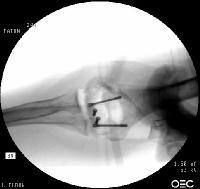

Open reduction via olecranon osteotomy.  The ulnar nerve is  retracted with a penrose drain. The articular surface was reconstructed, then secured to the shaft. After recovering the rotated anterior articular fragment, the anterior and posterior halves of the central articular component were secured with .062" pins. These pins were replaced one at a time with Herbert screws.

In similar steps, the reconstructed central articular component was secured to the proximal humerus with pins. Once satisfactory reduction was obtained (not yet, as seen here...), the pins were replaced by more Herbert screws. This allowed fixation of the purely osteochondral segments without prominent harware.

Click for larger image